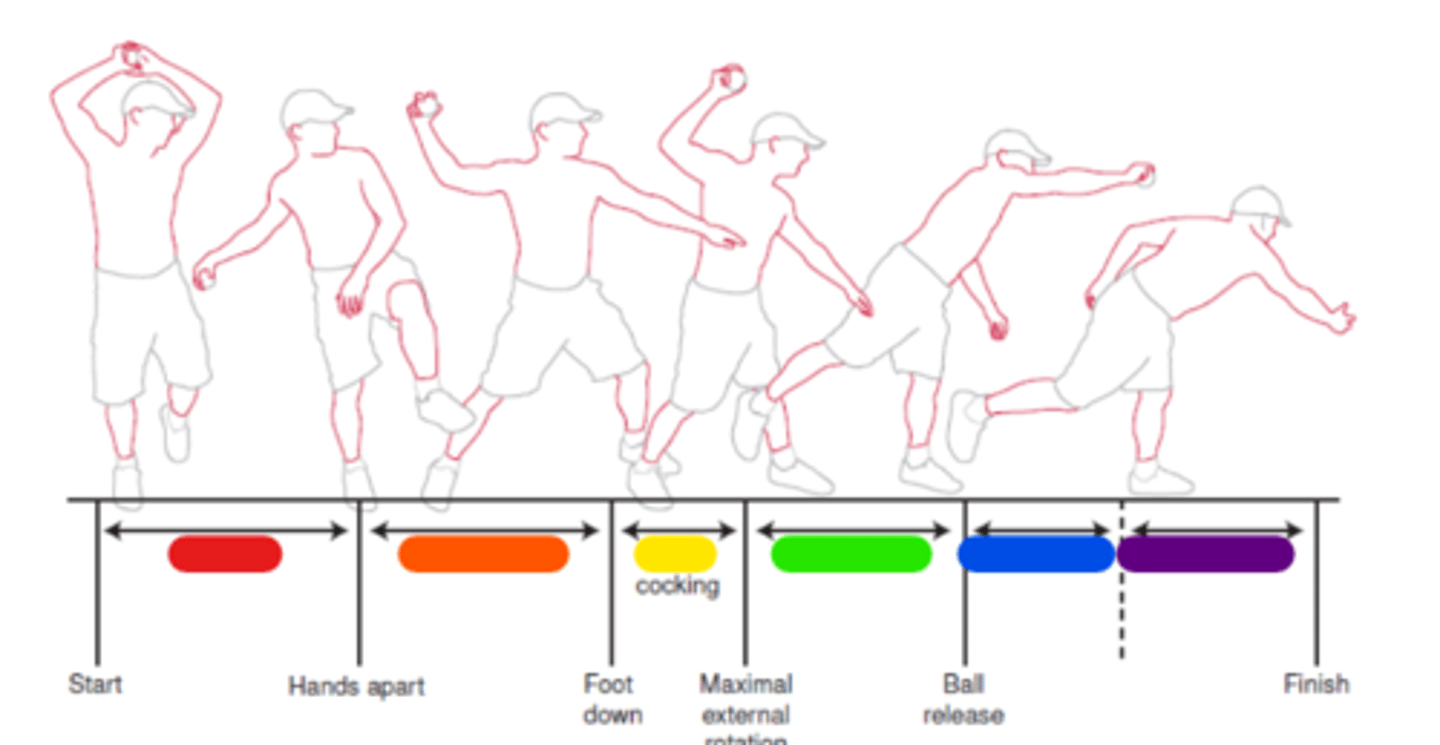

Windup

Red in image.

Early cocking

Orange in image.

Late cocking

Yellow in image.

Acceleration

Green in image.

Deceleration

Blue in image.

Follow through

Purple in image.